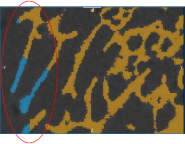

Closing the holes in an initial bone segmentation, including cortical pores and vascular canal inlets, and filling the inner areas of the segmentation, is the first step in the bone analysis workflow for accurately quantifying morphometric indices.

Cortical pore (circled)

- Enter the required threshold distance to close the cortical pores and vascular canal inlets in the Close holes smaller than edit box.

In some cases, an automated segmentation may result in voxels corresponding to trabecular bone erroneously labeled as cortical bone, as circled below, or vice versa.

Automated segmentation result